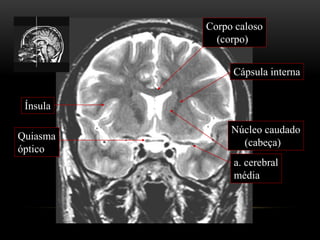

ANATOMIA TOPOGRÁFICA

Plano coronal

Corpo caloso

(corpo)

Quiasma

óptico

Cápsula interna

Núcleo caudado

(cabeça)

Ínsula

a. cerebral

média